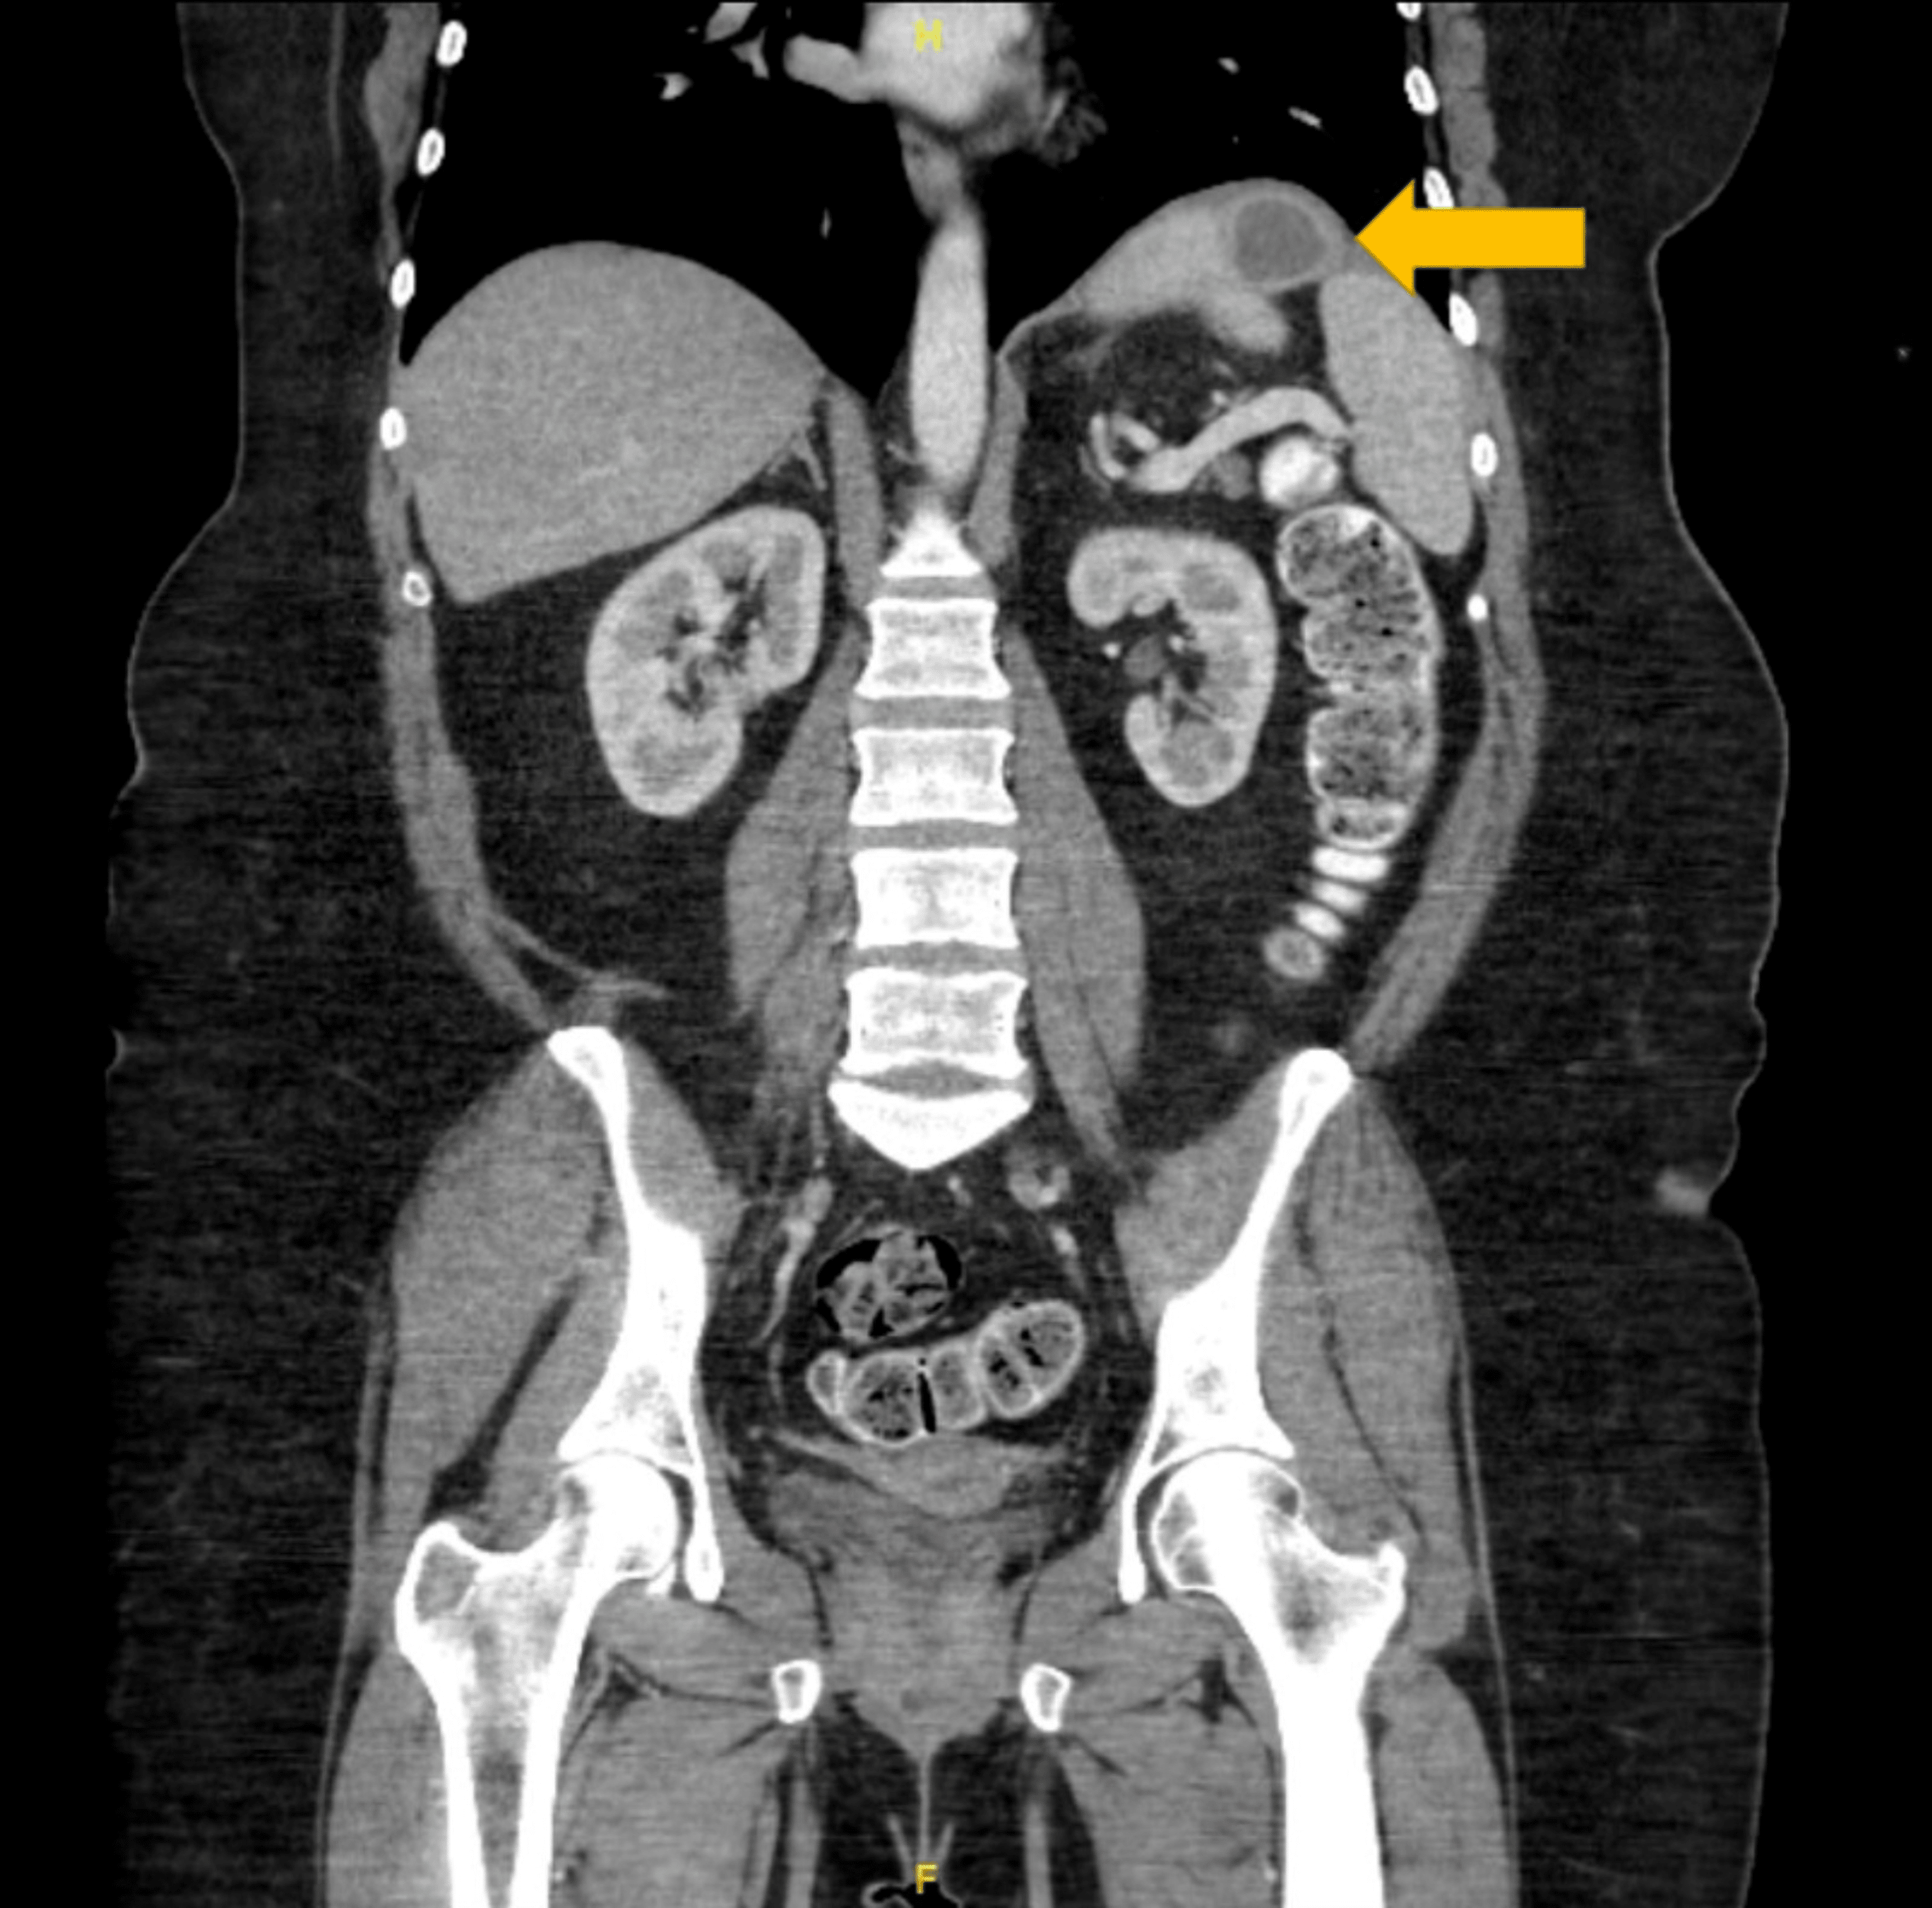

a CTscan of patient with fistula after sleeve gastrectomy. White Fistula After Gastric Sleeve — purpose to trace the clinical profile of fistula cases after sleeve gastrectomy (sg) and evaluate the. To trace the clinical profile of fistula cases after sleeve gastrectomy (sg) and evaluate the efficacy and safety of. — considering the rarity of gastropleural fistulas, this case report. Fistula After Gastric Sleeve.